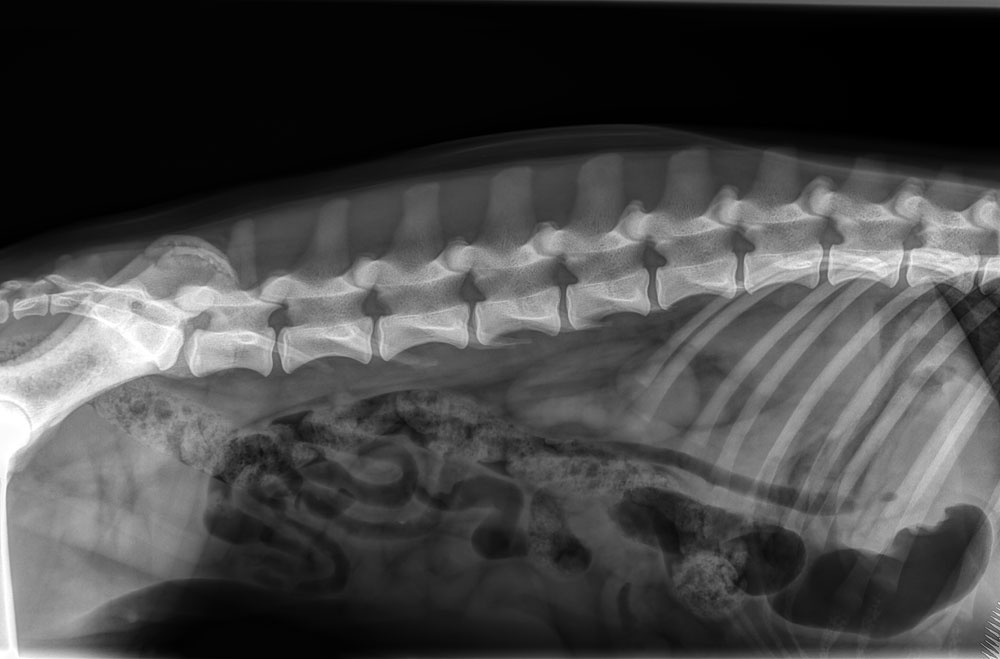

| Rug : | 7 wervels, normaal (foto) | |